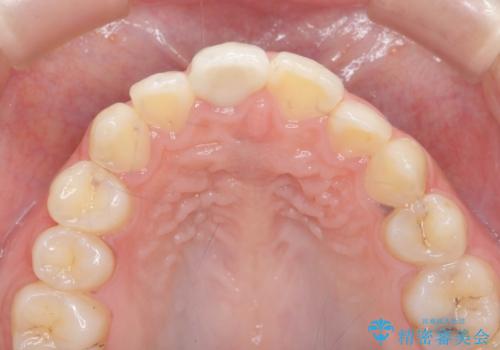

前歯の変色をキレイに セラミッククラウン審美治療

- 前歯の変色が気になる、見た目を改善したい!と審美性の回復を希望され来院されました。

ホワイトニングでは、周囲の歯との色調になじむほどには白くできないため、ジルコニアセラミッククラウンを用いて審美性を回復します。

周囲の歯の色調に調和した審美性の高いセラミッククラウンを製作することができました。